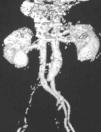

Patient 5. Pseudotrochanteric syndrome caused by ischemia. “An 81 year-old man was seen because of a refractory right trochanteric syndrome. Symptoms begun 1 month prior. An orthopedic colleague had administered 4 corticosteroid infitrations. In addition, he had intensive physical therapy treatment. He was unimproved and indeed felt worse. He arrived to the office in a wheel chair. He was interrogated with emphasis in the very onset of symptoms. He recalled that the initial pain was above the right iliac crest. Pain radiated to the foot where he had numbness and tingling of the great toe. Upon examination there was severe tenderness on the right greater trochanter. The right foot was cold. No pulses were noted on the pedal, posterior tibialis, popliteal and femoral arteries of the right leg. Pulses in the left leg were normal. A vascular surgeon was immediately consulted and an angio-TAC was performed. A complete occlusion of the right iliac artery was present (Fig. 8). The patient was brought to the operating room, a thrombectomy was performed and a stent was placed. There was immediate reperfusion of the leg and the next day the trochanteric pain had disappeared.